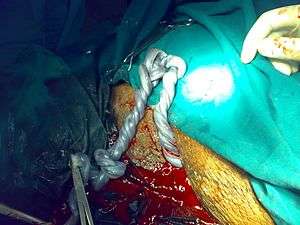

Constricted umbilical cord

When the umbilical cord is constricted (q.v. "accidents" above), the fetus experiences periods of hypoxia, and may respond by unusually high periods of kicking or struggling, to free the umbilical cord. These are sporadic if constriction is due to a change in the fetus' or mother's position, and may become worse or more frequent as the fetus grows. Extra attention should be given if mothers experience large increases in kicking from previous childbirths, especially when increases correspond to position changes.[18]

Regulating High blood pressure, diabetes and drug use may reduce the risk of a stillbirth. Umbilical cord constriction may be identified and observed by ultrasound, if requested.